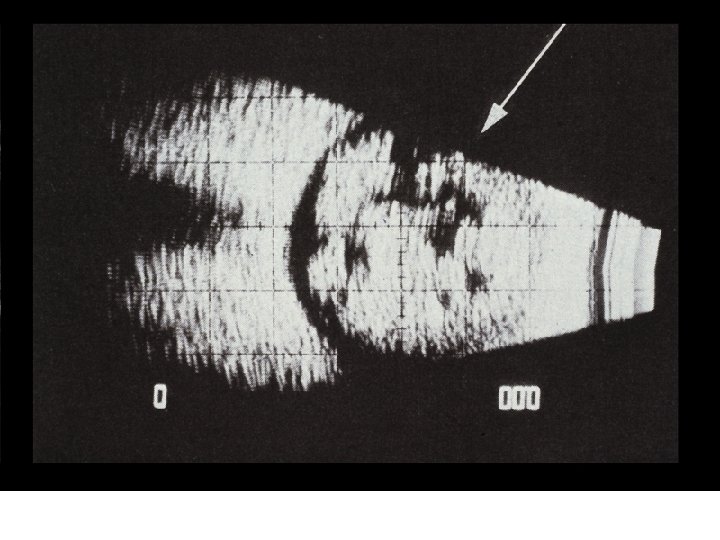

VII. PATHOLOGY AND AGE RELATED CHANGES z. A. Aging Changes y 1. Syneresis xa. a breakdown of the vitreous gel xb. fluid filled cavities form xc. 65 % of those over the age of 60 have syneresis xd. higher incidence in myopes

VII. PATHOLOGY AND AGE RELATED CHANGES xe. results in the fluid filled cavities enlarging and a possibility of the vitreous detaching from the retina xf. with detachment the patient reports "flashing lights" and "floaters" xg. more prone to retinal detachment